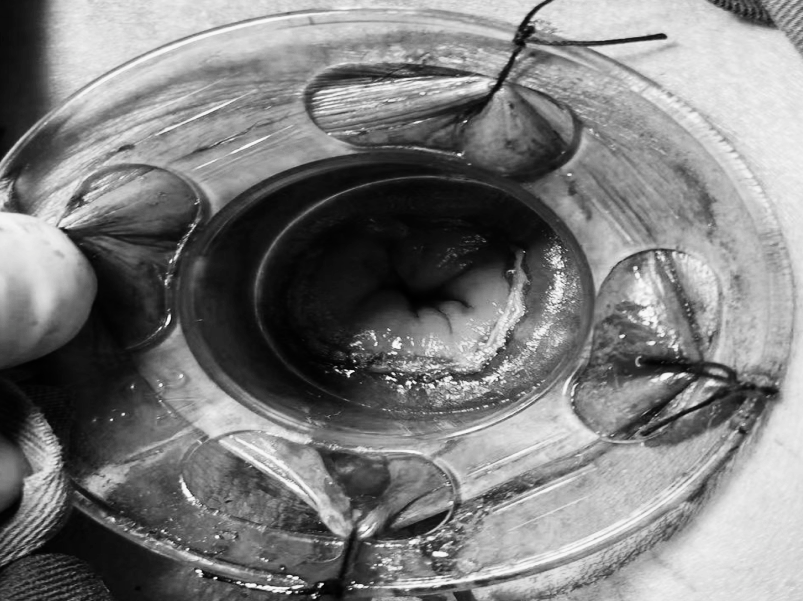

“医生,我爸妈只是关节痛,吃了点止痛药,怎么会胃穿孔要手术?”在普外科病房里,这样的疑问屡见不鲜,很多儿女都困惑不已:明明只是想帮老人缓解疼痛,一片孝心,怎么会把父母送进手术室? 今天,贵州航天医院普外科就来和大家聊聊如何科学、安全地使用止痛药,保护我们脆弱的胃肠,享受健康的生活! 【止痛药咋就把胃吃穿了?】 把胃想象成一个气球,胃黏膜就是内壁,很多止痛药(比如布洛芬、双氯芬酸钠等)会削弱这层内壁,胃酸就像强酸,没了胃黏膜这层内壁保护就会直接腐蚀胃,轻则糜烂、溃疡,重则出血、穿孔。 最危险的是:胃穿孔早期可能只是隐隐作痛、有点胀,容易被当成“老胃病”扛过去,等剧痛发作时,胃里的东西已流进腹腔,危及生命。 【为啥受伤的总是老年人?】 ※胃功能减退:上了年纪,胃黏膜变薄、修复能力下降。 ※多种药同吃:很多老人同时服用降压药、抗凝药,和止痛药叠加,胃根本扛不住。 ※自行用药:怕麻烦不去医院,按老经验或邻居推荐买药,隐患最大。 【安全用药“四要、四不要”】 四要—— ✔要查明原因:疼痛是警报,先看病再吃药,别盲目止痛。 ✔要保护胃:在医生指导下可加用胃黏膜保护剂(如奥美拉唑)。 ✔要饭后吃:务必饭后半小时服用,减少刺激。 ✔要见好就收:不疼了就停药,绝不长期吃。 四不要—— ❌不要自己加量:疼得厉害?找医生,别加药。 ❌不要混着吃:不同止痛药一起吃等于伤害叠加。 ❌不要长期吃:一般疼痛不连续吃超过一周。 ❌不要忽视警报:出现胃部不适、黑便、呕血、剧烈腹痛,立即停药就医! 【对付慢性疼痛,还有其他好办法】 ▶热敷、冷敷:简单有效,很多肌肉关节痛都管用。 ▶理疗、按摩:找正规中医推拿,效果不输止痛药。 ▶温和运动:散步、打太极,增强肌肉力量。 ▶转移注意力:养花、写字、聊天——当你不那么关注“痛”时,痛感往往会减轻。 【给子女的2点提醒】 ※管好药箱:定期清理过期药,搞清楚老人每天在吃什么药。 ※当好翻译:陪老人看病时,说清哪里痛、吃过啥药、效果如何。 止痛药是缓解疼痛的有效工具,但绝非“万能神药”。请一定记住:面对疼痛,“硬扛”不是办法,“乱吃”更是大忌,守护胃肠健康,从科学用药开始。 注:本文仅为健康科普,旨在提高公众用药安全意识,具体用药请务必咨询专业医生,遵医嘱执行。 贵州航天医院普外科专家简介 高大勇 普外科(肛肠外科)学科带头人、名誉主任,主任医师、教授 临床擅长:对中西医结合诊治肛肠学科各种常见病、多发病及疑难杂症等具有丰富的临床经验。 原遵义市第一人民医院(遵义医科大学第三附属医院)、遵义市中医院肛肠科主任。中华中医药学会肛肠分会常委,全国中医肛肠学科名专家,中国健康促进与教育协会肛肠分会常委,中国康复医学会肛肠疾病康复专业委员会常委,中国民间中医医药研究开发协会肛肠分会副秘书长,中国医师协会中西医结合肛肠医师专业委员会常委,国家二级心理咨询师,贵州省第一批中医名医工作指导老师,遵义市名中医,遵义市肛肠学会会长,遵义市肛肠质控中心名誉主任,遵义市中西医结合学会名誉会长,遵义市健康科普专家,原贵州省中西医结合学会肛肠分会副主任委员、贵州省中医肛肠质控中心副主任、遵义市医学会医疗鉴定委员会专家、遵义市卫生系列高评委。发表论文30余篇,主编和参编医学著作5本,主持省级科研课题2项、市级科研课题2项、院级科研课题1项。 梁 跃 普外科党支部书记、主任,主任医师 临床擅长:对普外科各类肿瘤手术具有丰富的临床经验。 毕业于遵义医学院,遵义市医学会小儿外科学分会常务委员,遵义市肛肠协会理事,遵义市医学会核医学分会(第二届)委员会委员;荣获第三期“黔医人才计划”优秀学员称号;主持市级课题1项,完成省级课题1项,在国内各类刊物上发表论文10余篇。 钱科洪 民盟盟员,普外科副主任医师 临床擅长:从事普外科临床工作30余年,对各类普外科疾病的诊治、乳腺、甲状腺、胃十二指肠、结直肠等疾病及疑难杂症具有丰富的临床经验。 毕业于遵义医学院临床医疗系,2009年前往中山大学附属第一医院微创外科进修学习,在国内各专业期刊发表论文数篇。 贵州航天医院普外科简介 基本情况 贵州航天医院普外科成立于1968年,前身属于航天部O61基地3417医院外一科,1998年3417医院、3427医院合并后更名为普外科,下设胃肠外科、肛肠外科2个亚专业科室,拥有在全市较为先进的专科设备和技术,是中国疝病专科联盟单位,贵州医科大学附属医院胃肠外科专科联盟单位。开放床位40张,配备医护人员21人。 专科特色 普外科致力于胃肠及肛肠疾病的外科临床诊治及科研,以腹腔镜微创外科技术为本,形成以快速康复治疗胃肿瘤、结直肠肿瘤、小肠肿瘤、直肠脱垂、肥胖病、急腹症、各类疝、痔、瘘等专科特色,同时注重胃肠疾病尤其是结直肠恶性肿瘤的基础研究和临床转化研究,总体诊断和治疗水平在区域同级医院居于领先水平。 开展手术:腹腔镜下胃癌根治术,腹腔镜下袖状胃切除术,腹腔镜下胃肠道间质瘤切除术,腹腔镜下结、直肠癌根治术,胃癌、结直肠癌的精准治疗,腹腔镜下小儿疝气、成人疝修补术,腹腔镜下阑尾手术,内痔的硬化注射治疗及痔疮的微创治疗:ATH、PPH、TST,直肠脱垂的各种手术治疗,难治性伤口VSD技术,鼻胃肠管、肠梗阻导管置入术,肛肠术后间歇性导尿技术,并引进了中医适宜技术,也为各种化疗患者提供输液港安装,提高患者就医体验。 腹腔镜下腹股沟疝 无张力修补术 腹股沟疝里金斯坦 (Lichtenstein)手术 PPH微创术治疗环状混合痔 黏连性或炎性肠梗阻-肠梗阻导管 腹腔镜袖状胃切除 腹腔镜阑尾切除术 腹腔镜阑尾肿瘤切除术 腹腔镜下结肠癌根治术 诊疗范围 胃肿瘤、结直肠肿瘤、小肠肿瘤、肥胖症、各类急腹症、腹部外伤、腹壁疝、便秘、直肠脱垂、痔疮、肛瘘、肛裂等胃肠、肛肠外科疾病。 END